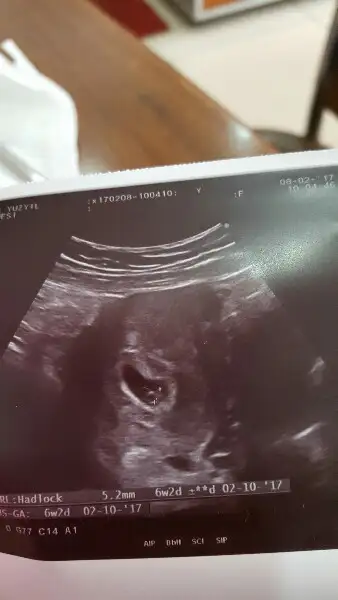

Merhaba 7. hafta görüntüsü benimde. Yorumlarsanız sevinirim :)

• IMG_1233.webp

IMG_1233.webp

5,4 KB · Görüntüleme: 206